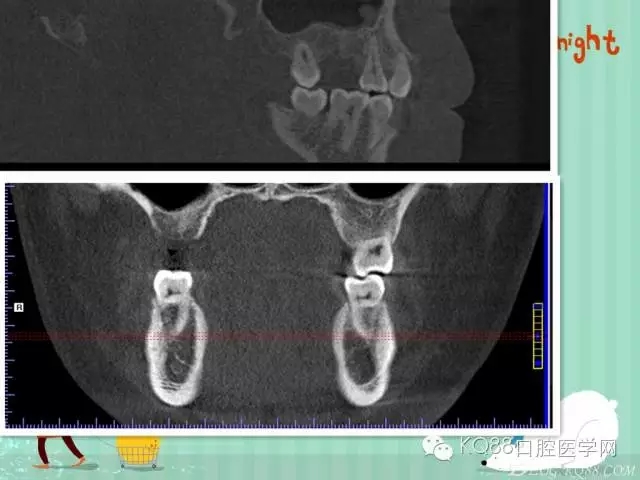

下面是拔牙前 CBCT

清晰可見(jiàn)根尖部陰影區(qū)域明顯。遠(yuǎn)中頰根

近中頰跟,同時(shí)可以看出離上頜竇比較近,且伴有骨缺損。

這個(gè)切面可以看到根裂。